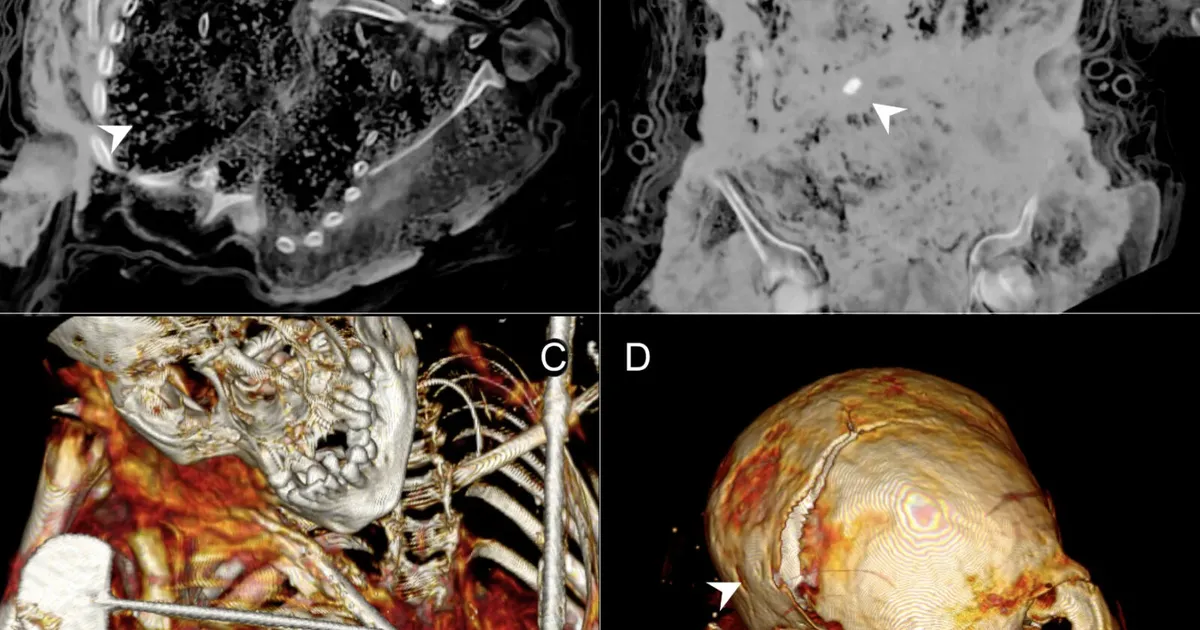

Inkad ohverdasid lapsi nende päid lömastades – sellega aga asi ei piirdunud

Ligikaudu viis sajandit tagasi toimunud inkade rituaalsed laste ohverdused on seni olnud tuntud peamiselt koloniaalajastu kroonikate vahendusel. Nüüd on nelja Andide kõrgustikus...